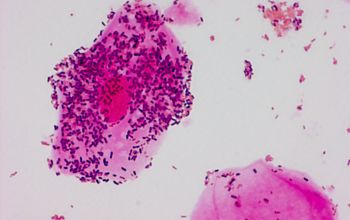

Gardnerella bakterija je mali, nepokretan gram-negativan bacil, a u normalnim uslovima je prisutan u materici i debelom crevu.  U svakoj zdravoj vagini, korisne bakterije – kao što je Lactobacillus, koji reguliše normalan vaginalni pH – koegzistira sa štetnim bakterijama u pažljivom balansu. Međutim, kada štetne bakterije počnu da se prenamnožavaju, javlja se gardnerella infekcija.

gardnella bakterija